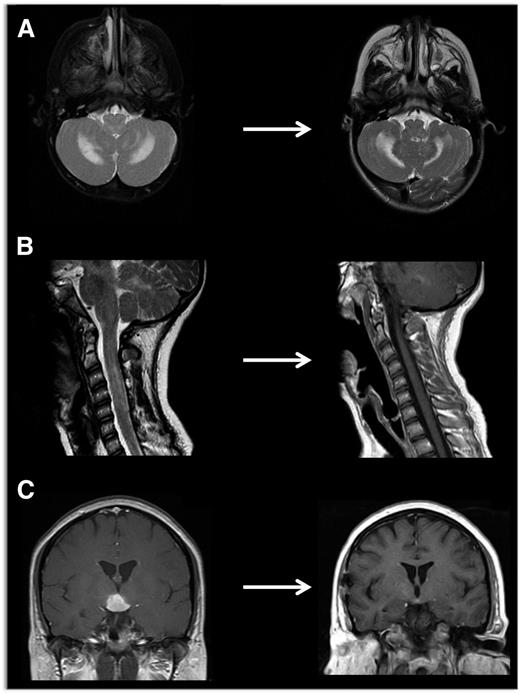

Neuroimaging of LCH lesions. These examples demonstrate typical manifestations of LCH CNS and spinal cord lesions. (A) Brain MRI demonstrates T2-hyperintensity in cerebellum classic for LCH neurodegenerative syndrome. In this case, the patient had radiologic and clinical response to treatment with cytarabine. (B) Spinal MRI demonstrates significant spinal cord lesions. This is a somewhat atypical case of a 13-year-old girl who had marginal response to cytarabine, then clofarabine. BRAF-V600E was detected in cells from the CSF, and the patient ultimately had radiologic and clinical response to vemurafenib. (C) Brain MRI demonstrates a pituitary mass classic for LCH, though differential diagnosis also includes germinoma, lymphoma, and pituitary hypophysitis. In this case, the lesion was biopsy proven to be LCH, and the patient responded to cytarabine therapy.